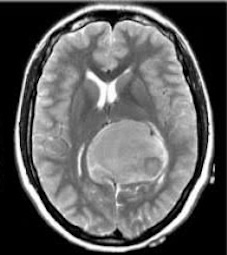

The Brain Tumor MRI Images dataset is a publicly available dataset on Kaggle555https://www.kaggle.com/datasets/sartajbhuvaji/brain-tumor-classification-mri/data. It contains MRI images of human brains divided into four categories: No Tumor, Pituitary Tumor, Benign Tumor, and Malignant Tumor. For our study, we selected three categories: No Tumor (NT), Benign Tumor (BT), and Malignant Tumor (MT). From each category, we chose three MRI images representing different parts of the brain that best illustrate the characteristics of each class. The categories included in this study are described as follows:

The Malignant Tumor (MT) category consists of MRI images showing cancerous tumors. These tumors are aggressive, can grow rapidly, and may spread to other parts of the brain or body. Malignant tumors require immediate and intensive treatment, such as surgery, chemotherapy, or radiotherapy. Differentiating malignant tumors from benign tumors is crucial, as it directly impacts the treatment strategy and can significantly affect patient outcomes.

Differentiating these categories is essential for early detection, accurate diagnosis, and effective treatment planning. By distinguishing between healthy brains, benign tumors, and malignant tumors, medical professionals can identify abnormalities more reliably, reduce misdiagnoses, and streamline medical care. In this study, we apply our divergence measure to differentiate between the selected MRI images, as illustrated in Figure 5. In Figure 5, the first row shows MRI images from NT patients, the second row shows images from BT patients, and the third row shows images from MT patients.

Using the divergence measure, we calculated estimates for each pair of MRI images and compared the three categories. For calculation, each grayscale image is represented by its pixel intensity values (scaled to [0,1]). These values are flattened into a one dimensional vector and used as the sample data for subsequent analysis. For any two images, denoted data1 and data2, we then computed an empirical based divergence estimate. The resulting values are presented in Tables 4, 5, and 6. A higher value of the divergence estimate indicates a greater likelihood of a tumor. These results demonstrate that the divergence measure can serve as an effective tool for detecting tumors in medical image data.

Table 5. Estimated Divergence Measure Values for Pairs of Different Classes in Axial View Brain MRIs

NT2 BT2 MT2

NT2 0 0.024 0.093

B2 0.024 0 0.046

MT2 0.093 0.046 0